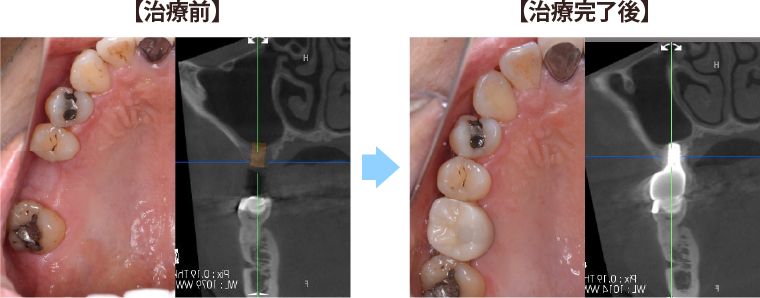

①右上6番が無く、骨の高さが少ない症例

骨の高さが少し足りず、このままではインプラントが骨からはみ出てしまう。

-

インプラント埋入と同時に骨の高さを増やす手術(上顎洞底挙上術)を併用し、

1回の手術でインプラントを埋入できました。

数か月ほど骨との結合を待った後に、かぶせ物を製作しています。

数年経過しても、全く違和感なく食事を楽しめています。

| 治療期間 : | 3ヶ月 |

| メリット : | ブリッジや入れ歯に比べて、両隣の歯を削ること無く、強い歯を再建することができる。 入れ歯やブリッジに比べて自然なかみ合わせを得られる。 概して入れ歯やブリッジより長持ちし、他の残存歯における負担も減らすことで、残存歯本来の寿命を全うできることが多い。 虫歯にならない。 |

| リスク・副作用 : | 手術が必要であり、感染のリスクを伴う。 術後に一時的に腫れたり痛みが出ることがある。 治療完了までに数か月の期間を要する。 自費治療であり、保険治療より高額である。 インプラントも歯周病になることがある。 |

| 費用(自費治療分): | 合計金額 ¥473,000(税込) (ソケットリフト法併用、SLActive加算、ジルコニア冠の場合) |